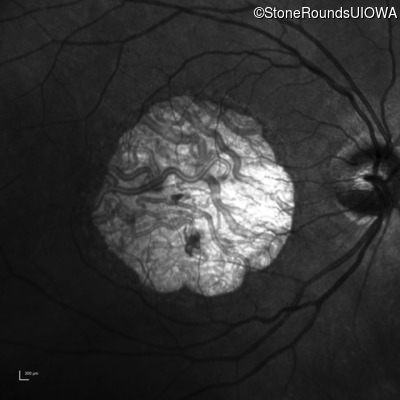

Infrared Fundus Photograph - Right - 20/63 -2

Exemplar